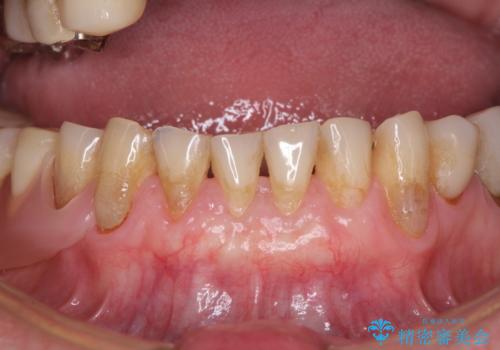

前歯の歯肉退縮 歯肉移植による根面被覆

担当医 藤巻太一朗